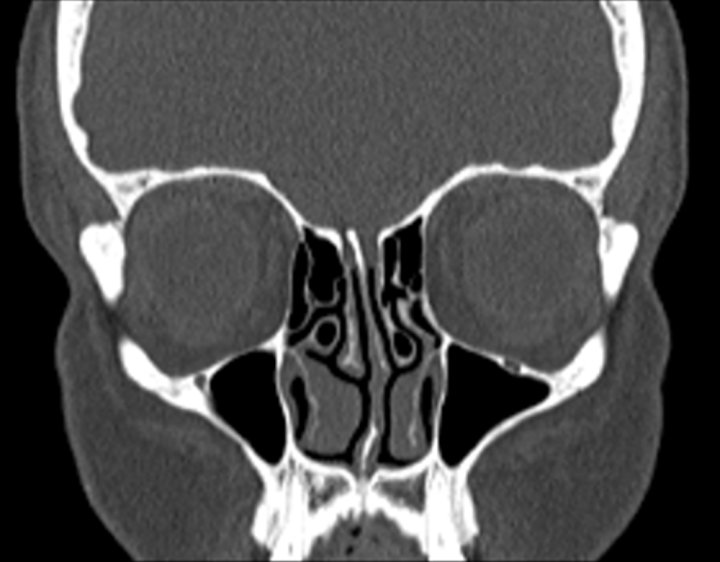

Click any image for labels.